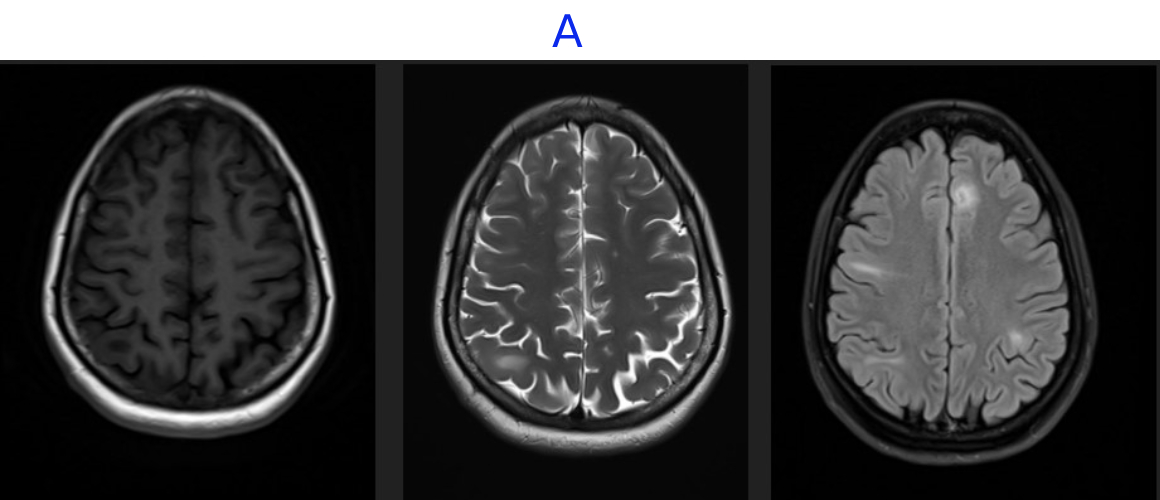

• A. MR BRAIN

• A. There are multiple cortical and subcortical lesions seen in both cerebral hemispheres, most prominently involving the frontal and parietal lobes. These lesions demonstrate T2/FLAIR hyperintensity with corresponding T1 hypointensity, without associated mass effect. No evidence of any diffusion restriction or post-contrast enhancement.

• C. Areas of mild cortical thickening and blurring of the gray–white junction, consistent with focal cortical dysplasia